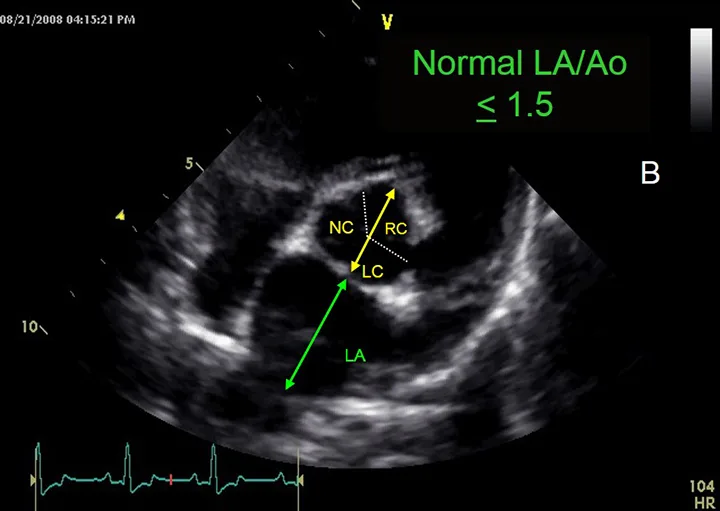

Ultrasound image with labels demonstrating measurement of the aorta in yellow and the left atrium in green.

FIGURE 3B

Assessment of left atrial size. This image demonstrates the measurement of the aorta (yellow arrow) and left atrium (green arrow).

• Image seen: In the view shown in this figure, the ratio of the left atrium (LA) to the aorta (Ao) should be <1.5:1 (also see Figure 3B).1

Assessing Left Atrial Size

To assess the size of the left atrium, the transverse diameters of the aorta and left atrium are measured in the right sided short-axis view. Of note, other views can be used to obtain measurements, but these are the author’s preferred views. Measurements are taken in early ventricular diastole using the first frame after aortic ejection, where the Ao appears as a symmetric three-leaf clover with closed aortic valves and a teardrop-shaped LA.

1. To measure Ao, the first caliper is placed at the midpoint of the convex curvature of the wall of the right aortic sinus. The caliper cross is positioned as close as possible to the blood-tissue interface.

2. The second caliper is positioned at the point where the aortic wall and the noncoronary and left coronary aortic cusps merge. This measurement point is defined by a slight increase in echogenicity where the three structures merge.

3. The LA is measured from this point by extending the Ao line to the blood-tissue interface of the LA wall.

4. If a pulmonary vein enters the LA at the desired measurement point, the caliper is placed either on an extrapolation of the atrial border or immediately medial or lateral to the vein.2